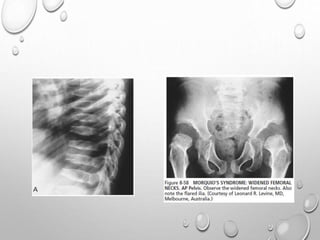

• 1. DYSPLASTIC OR SQUARE

ILIAC BONES

2. NARROW SACRO-SCIATIC

NOTCHES

3. FLAT BILATERAL

ACETABULAR ROOFS

4. SHORT BOTH FEMORAL

NECKS

5. CHAMPAGNE GLASS-

SHAPED PELVIC CAVITY